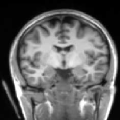

To compare the proposed approach to the mSENSE333SENSE reconstruction implemented by the Siemens scanner, software ICE, VB 17. one, Fig. 1 illustrates coronal anatomical slices reconstructed with both algorithms while turning off the temporal regularization in 4D-UWR-SENSE, so resulting in the so-called 3D-UWR-SENSE approach. Red circles clearly show reconstruction artifacts and noise in the mSENSE reconstruction, which have been removed using our 3D-UWR-SENSE approach. Comparison may also be made through reconstructed slices for and , as well as with the conventional acquisition (). This figure shows that increasing generates more noise and artifacts in mSENSE results whereas the impact on our results is attenuated. Artifacts are smoothed by using the continuity of spatial information across contiguous slices in the wavelet space. Depending on the used wavelet basis and the number of vanishing moments, more or less (4 or 8 for instance) adjacent slices are involved in the reconstruction of a given slice. For instance, using Symmlet filters of length 8 (4 vanishing moments) as in the conducted experiments here, 8 adjacent slices are involved in reconstructing a given slice. However, it is worth noticing that the introduced smoothing is anisotropic, in contrast to standard Gaussian smoothing that could be applied to anatomical data. Fig. 1 also compares 3D-UWR-SENSE and mSENSE reconstructed slices when applying additional spatial smoothing to the later with a mm3 Gaussian kernel. Comparisons clearly show that, even at such low spatial smoothing level, mSENSE images suffer from a significant blur. Moreover, the artifact present at for mSENSE (left red circle) is spread out but not fully removed by applying isotropic spatial smoothing.

In order to evaluate the impact of such smoothing, classification tests have been conducted based on images reconstructed with both methods. Gray and white matter classification results using the Morphologist 2012 pipeline of -MRI toolbox of Brainvisa software444http://brainvisa.info at and are compared to those obtained without acceleration (i.e. at ), considered as the ground truth. Displayed results in Fig. 2 show that classification errors occur due to reconstruction artifacts for mSENSE, especially at . Results show that the gray matter is better classified using our 3D-UWR-SENSE algorithm especially next to the artifact into the red circle (Fig. 2 []), which lies at the frontier between the white and gray matters. Moreover, reconstruction noise with mSENSE in the centre of the white matter (left red circle in Fig 2 []) also causes miss-classification errors far from the gray/while matter frontier. However, at and classification performance is rather similar for both methods, which confirms the ability of the proposed method to attenuate reconstruction artifacts while keeping classification results unbiased.

To further investigate the smoothing effect of our reconstruction algorithm, gray matter interface of the cortical surface has bee extracted using the above mentioned BrainVISA pipeline. Extracted surfaces (medial and lateral views) from mSENSE and 3D-UWR-SENSE images are show in Fig. 3 for . For comparison purpose, we provide results with mSENSE at as ground truth.